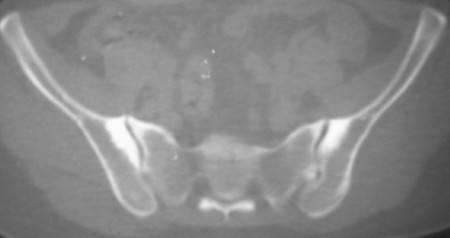

标题: CT7246: F,30岁,下腰痛,同事的片子,请老师们看看,初 [打印本页]

标题: CT7246: F,30岁,下腰痛,同事的片子,请老师们看看,初

典型的致密性髂骨炎

典型的双侧骶髂关节致密性骨炎.

何谓髂骨致密性骨炎?髂骨致密性骨炎是发生于髂骨耳状关节部分的骨质密度增高性疾病。病因迄今不明,可能与妊娠、机械性劳损、病灶性炎症有关。本病好发于20~35岁的育龄妇女,偶见男性。

髂骨致密性骨炎的临床表现与体征:腰骶部疼痛,多呈慢性、间歇性酸痛、隐痛,可向一侧或双侧臀部及大腿后侧扩散,但不沿坐骨神经方向放射,步行、站立、负重及劳累后加重,咳嗽、打喷嚏不能使疼痛明显加重,休息后症状减轻。患者腰骶角加大,局部有压痛和肌紧张,骨盆分离和挤压试验阳性,“4”字试验阳性,化验检查多在正常范围内。x线检查,骶髂关节间隙整齐清晰,靠近骶髂关节面中的髂骨耳状关节部分骨质密度增高,呈均匀浓白边缘清晰的骨质致密带,骨小梁消失,无骨质破坏。本病应注意与早期强直性脊柱炎、骶髂关节结核相鉴别。